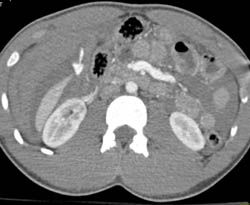

Portal Vein Infiltrated in Hilum